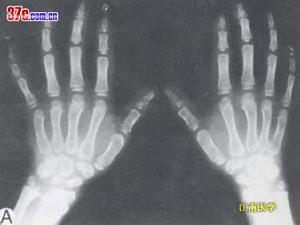

X線表現 特徵性的可見不透光的分散的或集合的密度增加的斑點,界限清晰,其大小由數毫米至大塊融合,占據了骨骺軟骨的部位。這些斑點要比正常的骨化中心出現得早。在肱骨下端,股骨上端表現較明顯,跗骨可以完全為不透光的斑點所代替,長骨幹縮短及肥厚,以股骨及肱骨更為明顯,骨端呈八字形,骺線不規則。扁骨及椎體表現相似,在鼻中隔、氣管及喉軟骨中亦可見鈣化,以致造成喉狹窄。隨年齡的增加,分散的斑點會逐漸融合,骨骺的病變亦見改善。